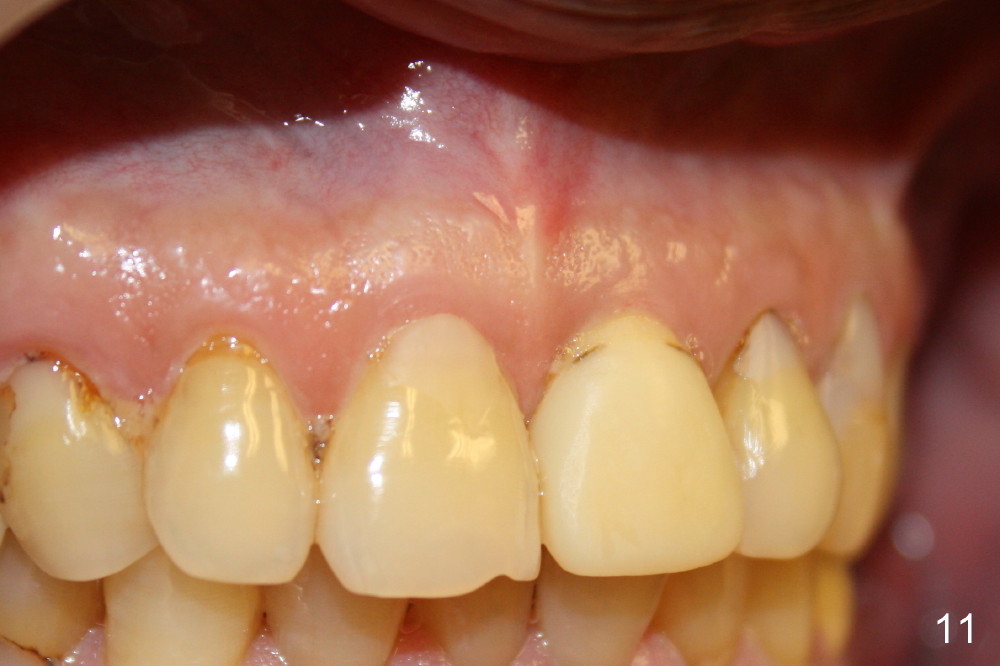

Postop tenderness lasts for two days. The palatal swelling is unnoticeable 7 days postop (Fig.9 *, as compared to A in Fig.8). The bone remains stable around the implant (Fig.10), while the gingiva healthy around the immediate provisional (Fig.11) 5 months postop. Due to insurance limit, the permanent restoration is delayed (16 months postop, Fig.12). The patient is satisfied with the function and appearance 3 years 8 months postop (21 months post cementation, Fig.13,14). PA is taken 4 years 1 month postop (2.5 years post cementation, Fig.15). The lamina dura forms from the most coronal threads (Fig.16). Although there is no bone loss around the implant (Fig.17), metal starts to show 5 years 2 months postop (Fig.18 ^), probably related to the buccal placement, too large the implant for the site or buccal plate atrophy (Fig.19).